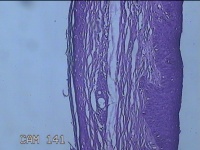

左眼外侧缘上肿物

性别

女

年龄

60岁

临床诊断

痣;疣

左眼上睑缘白色丘疹1年余。

灰白粉红色肿物0.8x0.3x0.2cm两个,表面光滑。